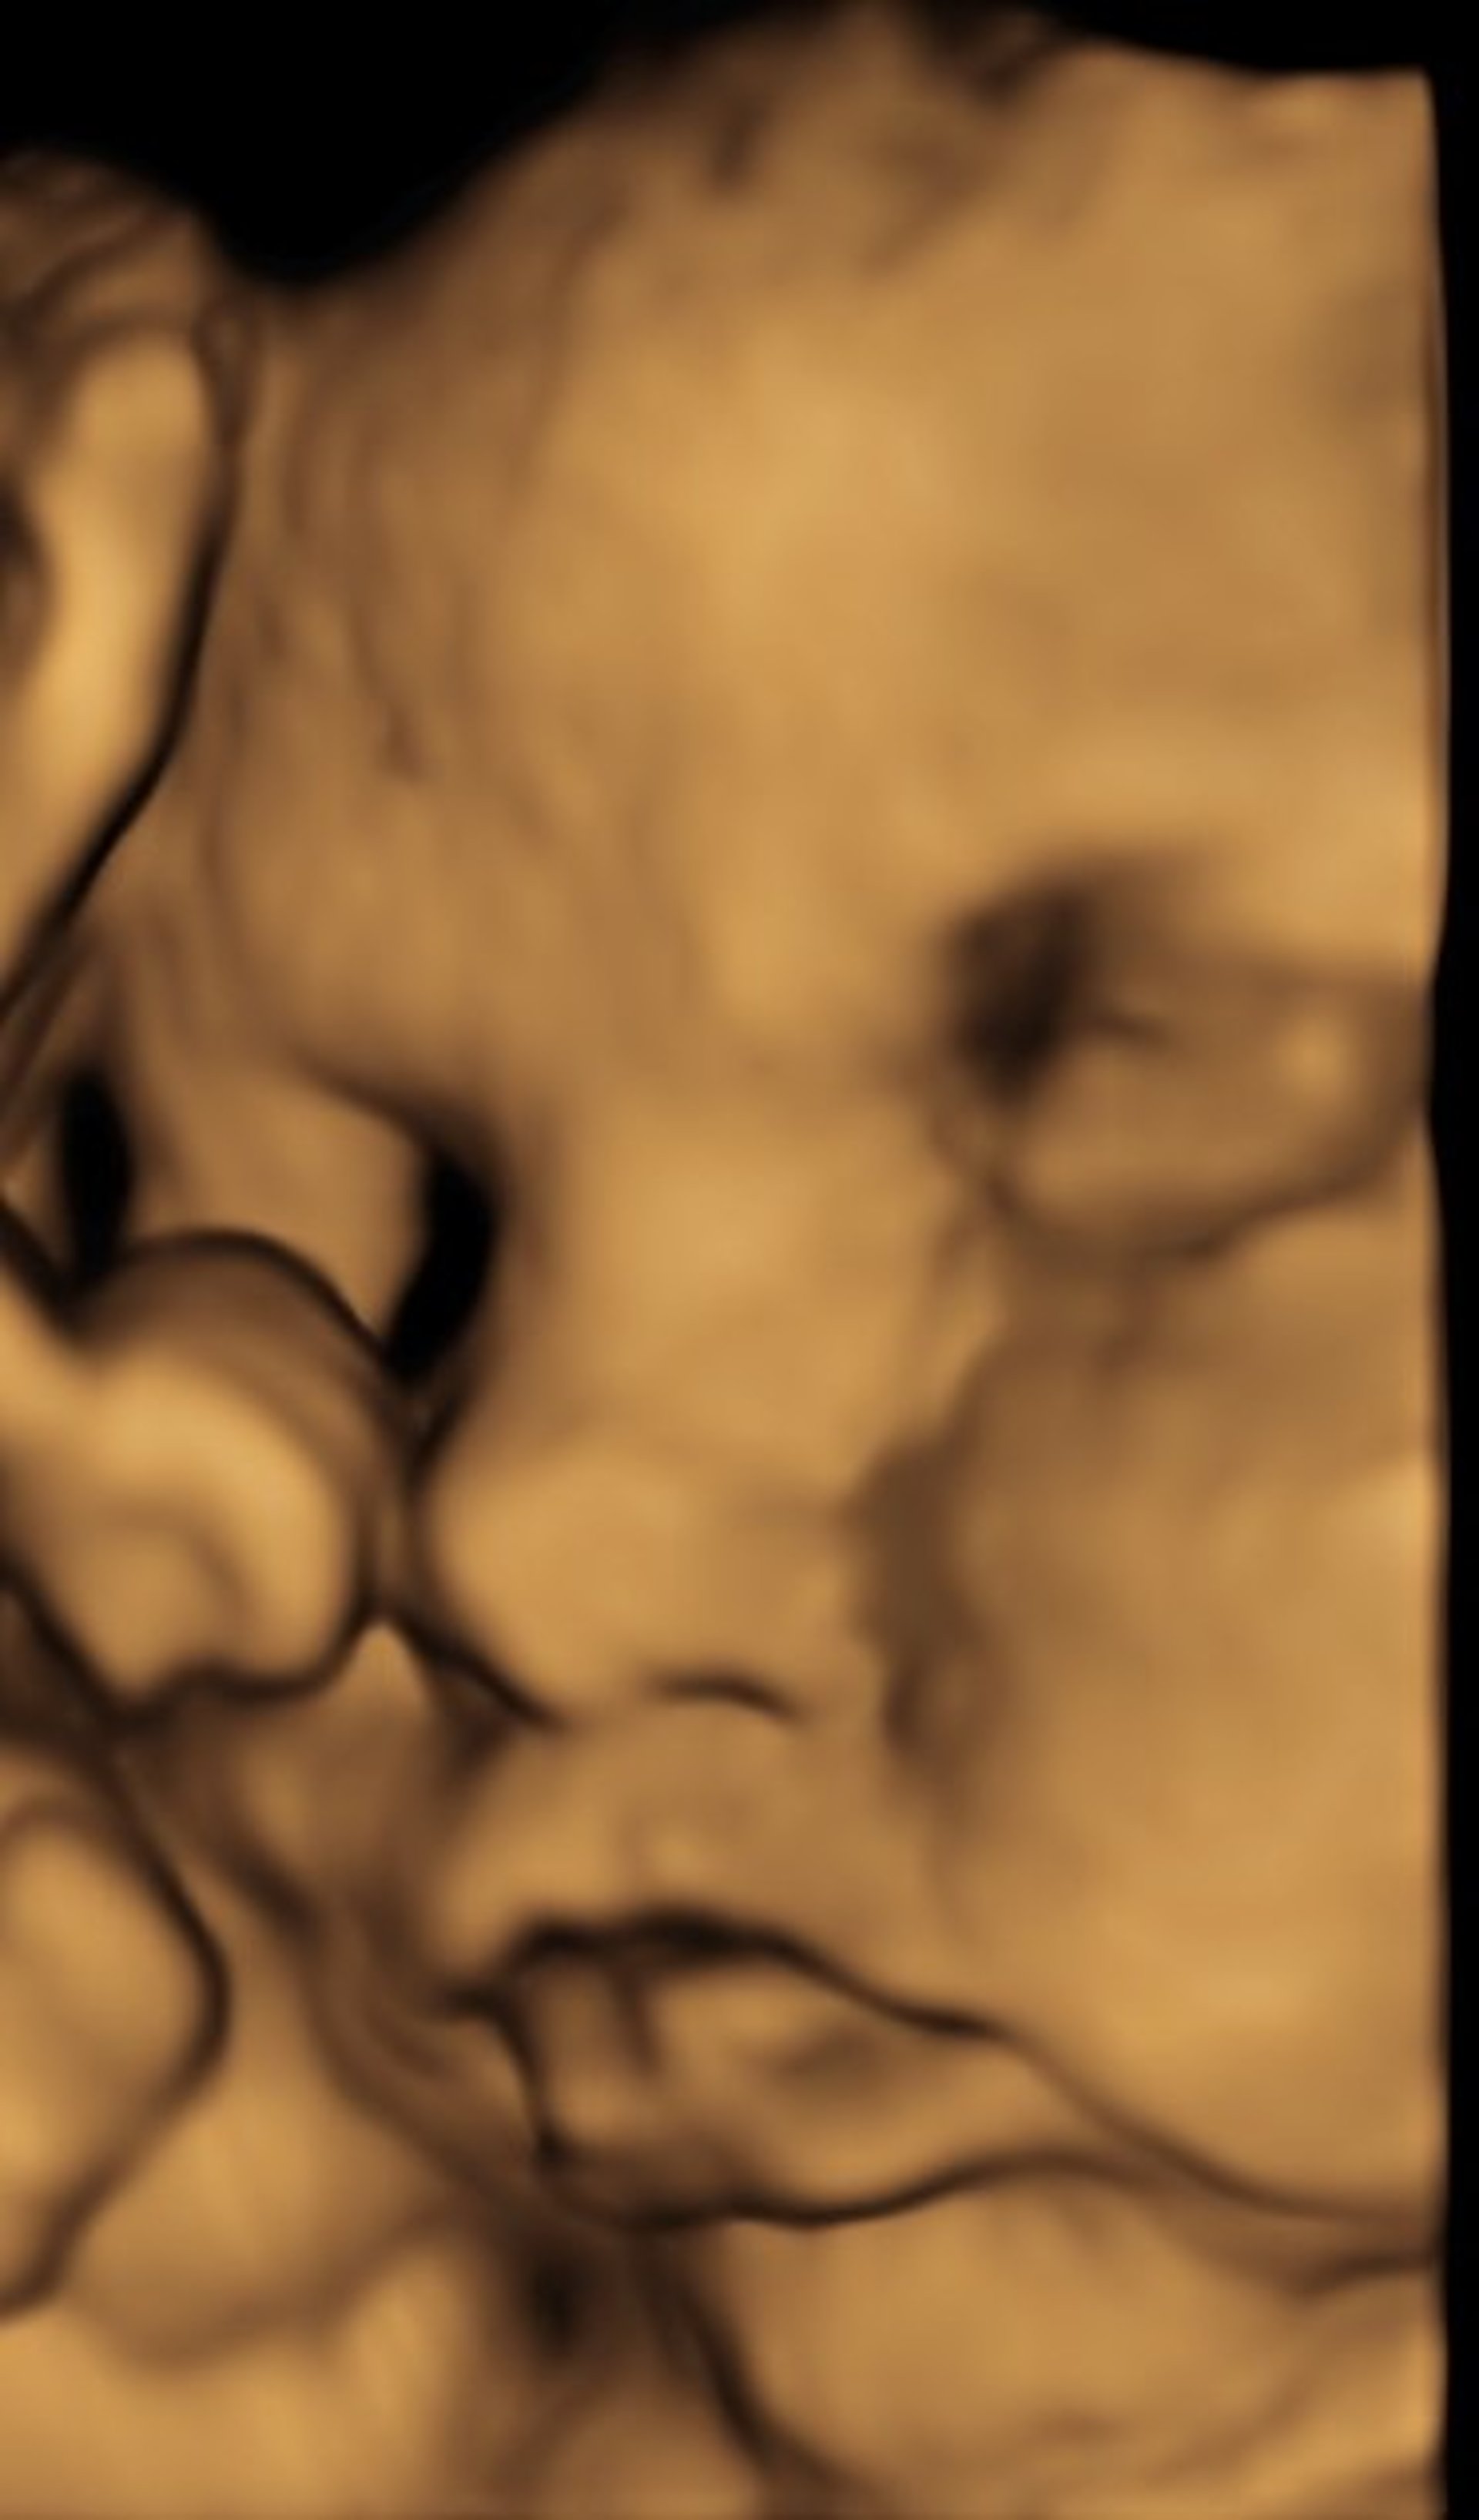

A magzati állapot gyors, egyszerű, és könnyen elérhető megítélésére leginkább alkalmas módszer az ultrahang vizsgálat. Segítségével mindenki számára könnyen értékelhető módon demonstrálható a magzati életjelenség a magzati szívműködés.

Az embrio fejlődése könnyen követhető, az első harmad végén nem csak számos genetikai rendellenességre utaló marker észlelhető, hanem a súlyos fejlődési rendellenességek 75%-a is felismerhető.

A várandósság második- és harmadik trimeszterében követhető a magzat fejlődése, növekedése, ellenőrizhető a magzati vérkeringés, ezáltal pontos információt nyerhetünk a magzati jólétről, illetve a magzati veszélyállapot fennállásáról.